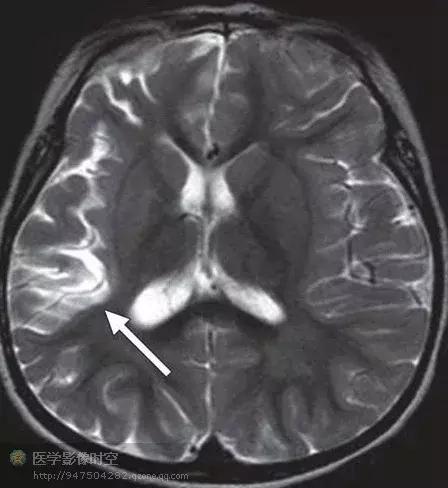

颞叶内侧硬化

颞叶内侧硬化是一种最常见的青少年癫痫病因。病理学上,特征是海马神经元丢失,胶质增生,也可以累及单侧穹窿和乳头体。临床上,病人常常具有皮质病变病史,例如颅内感染,外伤,或者5岁以前发生复杂性高热癫痫。初次治疗足以控制症状,部分病人实际上不需要治疗就可以痊愈。当癫痫复发的时候,常常为难治性。颞叶内侧硬化病人准确诊断受益最大,手术治疗具有90%的治愈率。

颞叶内侧硬化的诊断基于临床、脑电图和影像学检查。典型的磁共振成像特征包括T1WI上海马萎缩,T2WI上颞叶内侧高信号。然而,PET进行功能成像对海马硬化的敏感性更高,通常显示为高代谢区,大于海马范围。尤其是采用MR-PET融合图像时观察的效果更好。

图10 右侧海马硬化,颞肌呈现ⅠA型改变的15岁难治性癫痫男孩。图像质量受病人躁动影响欠佳。

图10a冠状T2WI显示右侧海马为T2高信号(箭)

图10b a稍后一点的冠状T2WI,右侧颞极白质(箭)与左侧正常脑白质(箭头)信号相比,呈现T2高信号。

图10c 冠状MR-PET融合图像显示右侧颞极低代谢活性。